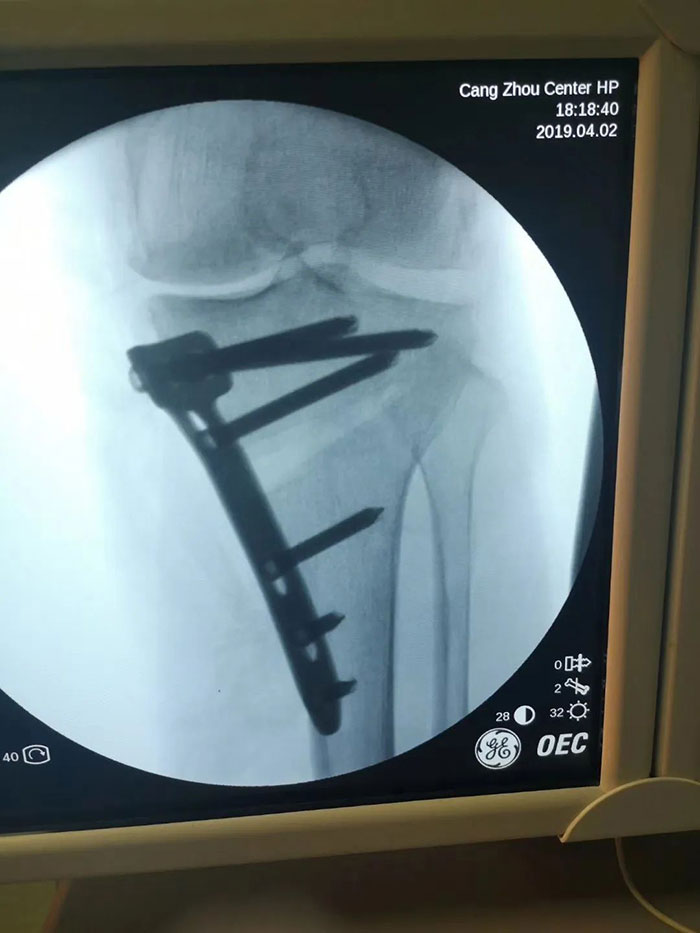

治療方案得到患者家屬的同意后,團(tuán)隊(duì)再次認(rèn)真地研究數(shù)字化影像,討論、設(shè)計(jì)并確定了截骨角度及手術(shù)方案。之后,在麻醉科的全力配合下關(guān)節(jié)外二科(骨五科)成功實(shí)施了手術(shù),經(jīng)過康復(fù)治療和功能訓(xùn)練后,患者恢復(fù)正常工作生活,行走自如。

王軍主任介紹說:脛骨高位截骨術(shù)(HTO)是保膝階梯治療過程中的一個(gè)常規(guī)手術(shù),技術(shù)成熟,是膝關(guān)節(jié)骨性關(guān)節(jié)炎階梯治療中的重要一步,這種手術(shù)保留原有膝關(guān)節(jié)的所有組織,通過矯正膝關(guān)節(jié)負(fù)重力線,阻止或減少關(guān)節(jié)軟骨的進(jìn)一步磨損,增加關(guān)節(jié)穩(wěn)定性,緩解疼痛,改善膝關(guān)節(jié)功能,保留了關(guān)節(jié)的全部韌帶,具有微創(chuàng)手術(shù)切口小、術(shù)后恢復(fù)快、功能恢復(fù)好等優(yōu)點(diǎn),使得術(shù)后關(guān)節(jié)功能和本體感覺接近于正常關(guān)節(jié)。同時(shí),關(guān)節(jié)鏡清理術(shù)能夠?qū)贾リP(guān)節(jié)內(nèi)的焦磷酸鈣化結(jié)晶、致炎因子、碎屑、游離體等進(jìn)行有效清除并修復(fù)損傷的半月板,有效緩解患者的臨床癥狀。